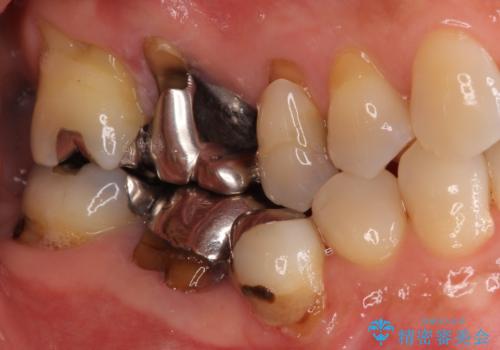

- 口腔内にある銀歯を全て外したいとのことで来院された患者様です。

土台に含まれている金属も含め、口腔内の金属は全て除去し、抜歯しなければならない歯は抜歯し、オールセラミッククラウンやセラミックインレーにて治療することとしました。

上下奥歯の抜歯を同時期に行わず、下顎の治療を終えてから上顎を抜歯して治療を進めたため、1年ほどの期間を要しました。